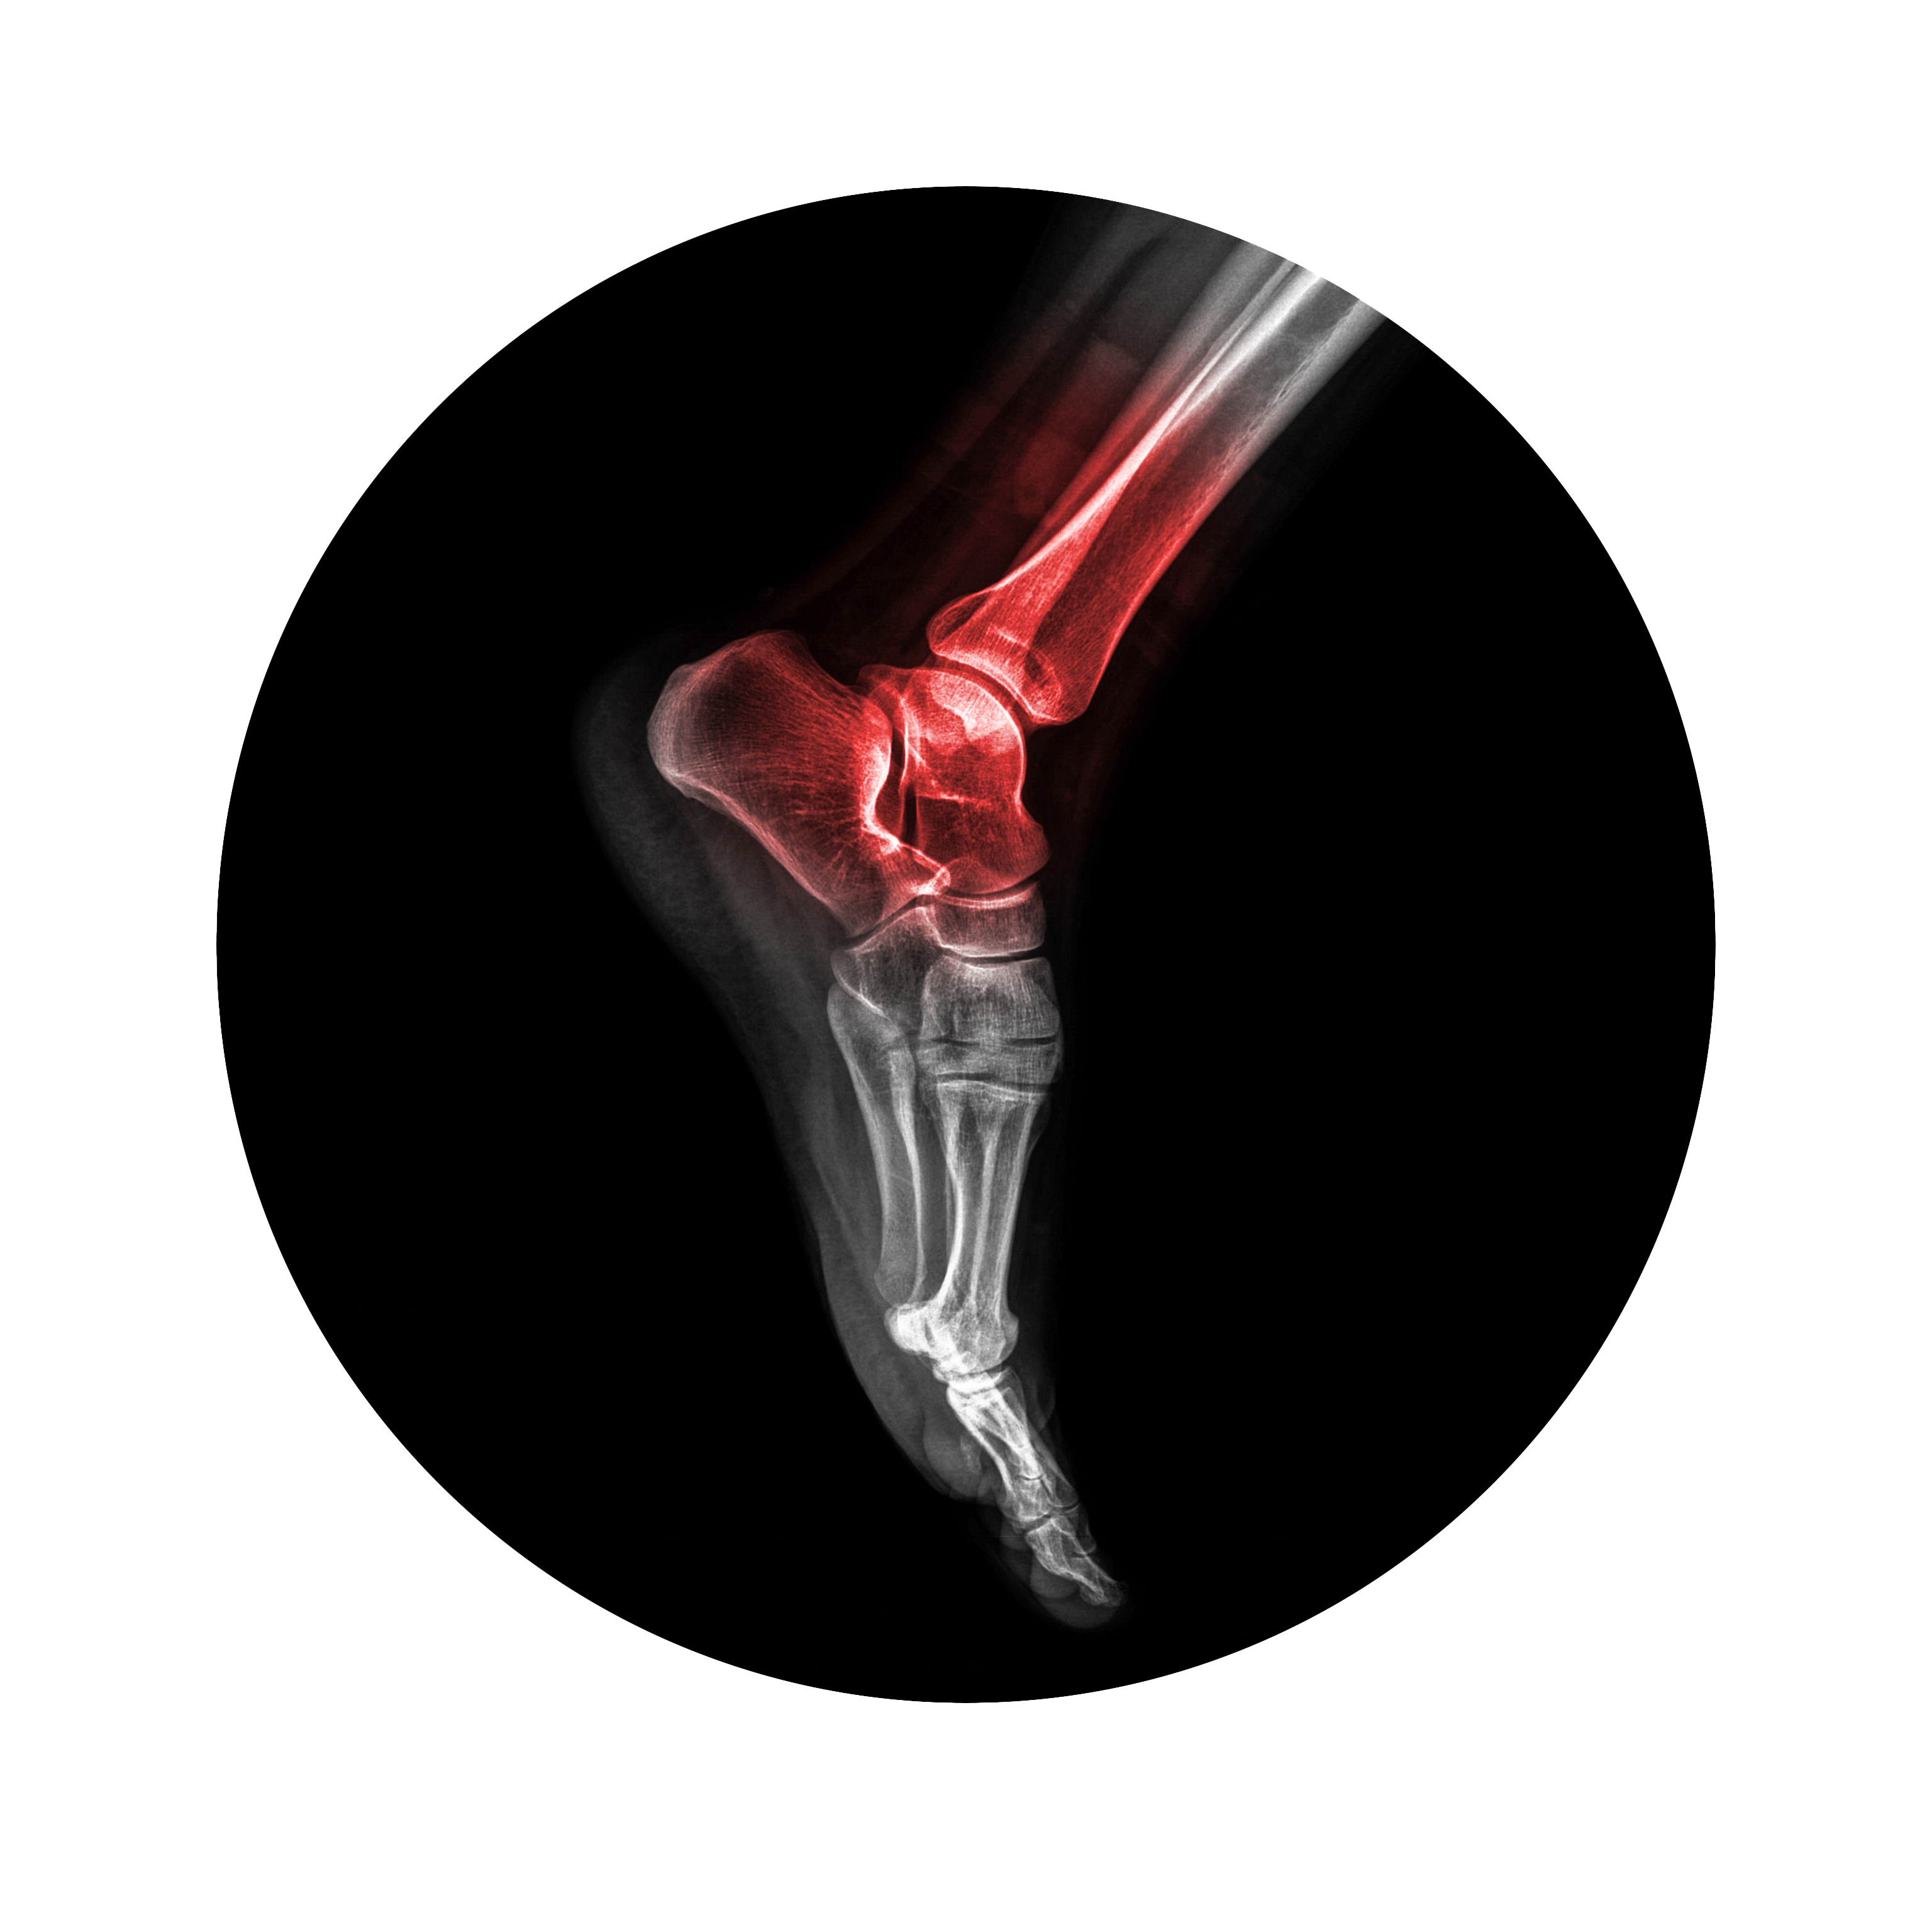

The quadriceps tendon is a strong rope-like fibrous tissue located at the top of the patella or kneecap that connects the quadriceps muscles to the kneecap. It works together with the quadriceps muscles to allow us to straighten our leg. The quadriceps muscles are the muscles located at the front of the thigh.

To identify a quadriceps tendon rupture, your doctor will review your medical history and perform a physical examination of your knee. Some imaging tests such as an X-ray or MRI scan may be ordered to confirm the diagnosis. An X-ray of the knee is taken to determine the position of the kneecap and an MRI scan is done to view the extent and location of the rupture.